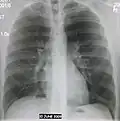

Normal AP CXR